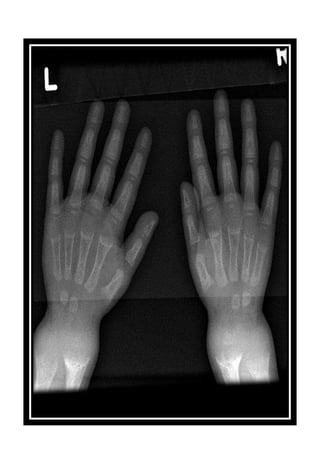

Radiological features of scurvy:

Generalized osteopenia

Cortical thinning: pencil thin cortex

Periosteal reaction due to subperiosteal

hemorrhage

Scorbutic rosary: expansion of the

costochondral junctions

Hemarthrosis

Wimberger ring: circular, opaque, radiological

shadow surrounding epiphyseal centers of

ossification, which may result from bleeding

Frankel line: dense zone of

provisional calcification

Trummerfeld zone: lucent

metaphyseal band underlying

frankel line.

Pelken spur: metaphyseal spurs

which result in cupping of the

metaphysis.